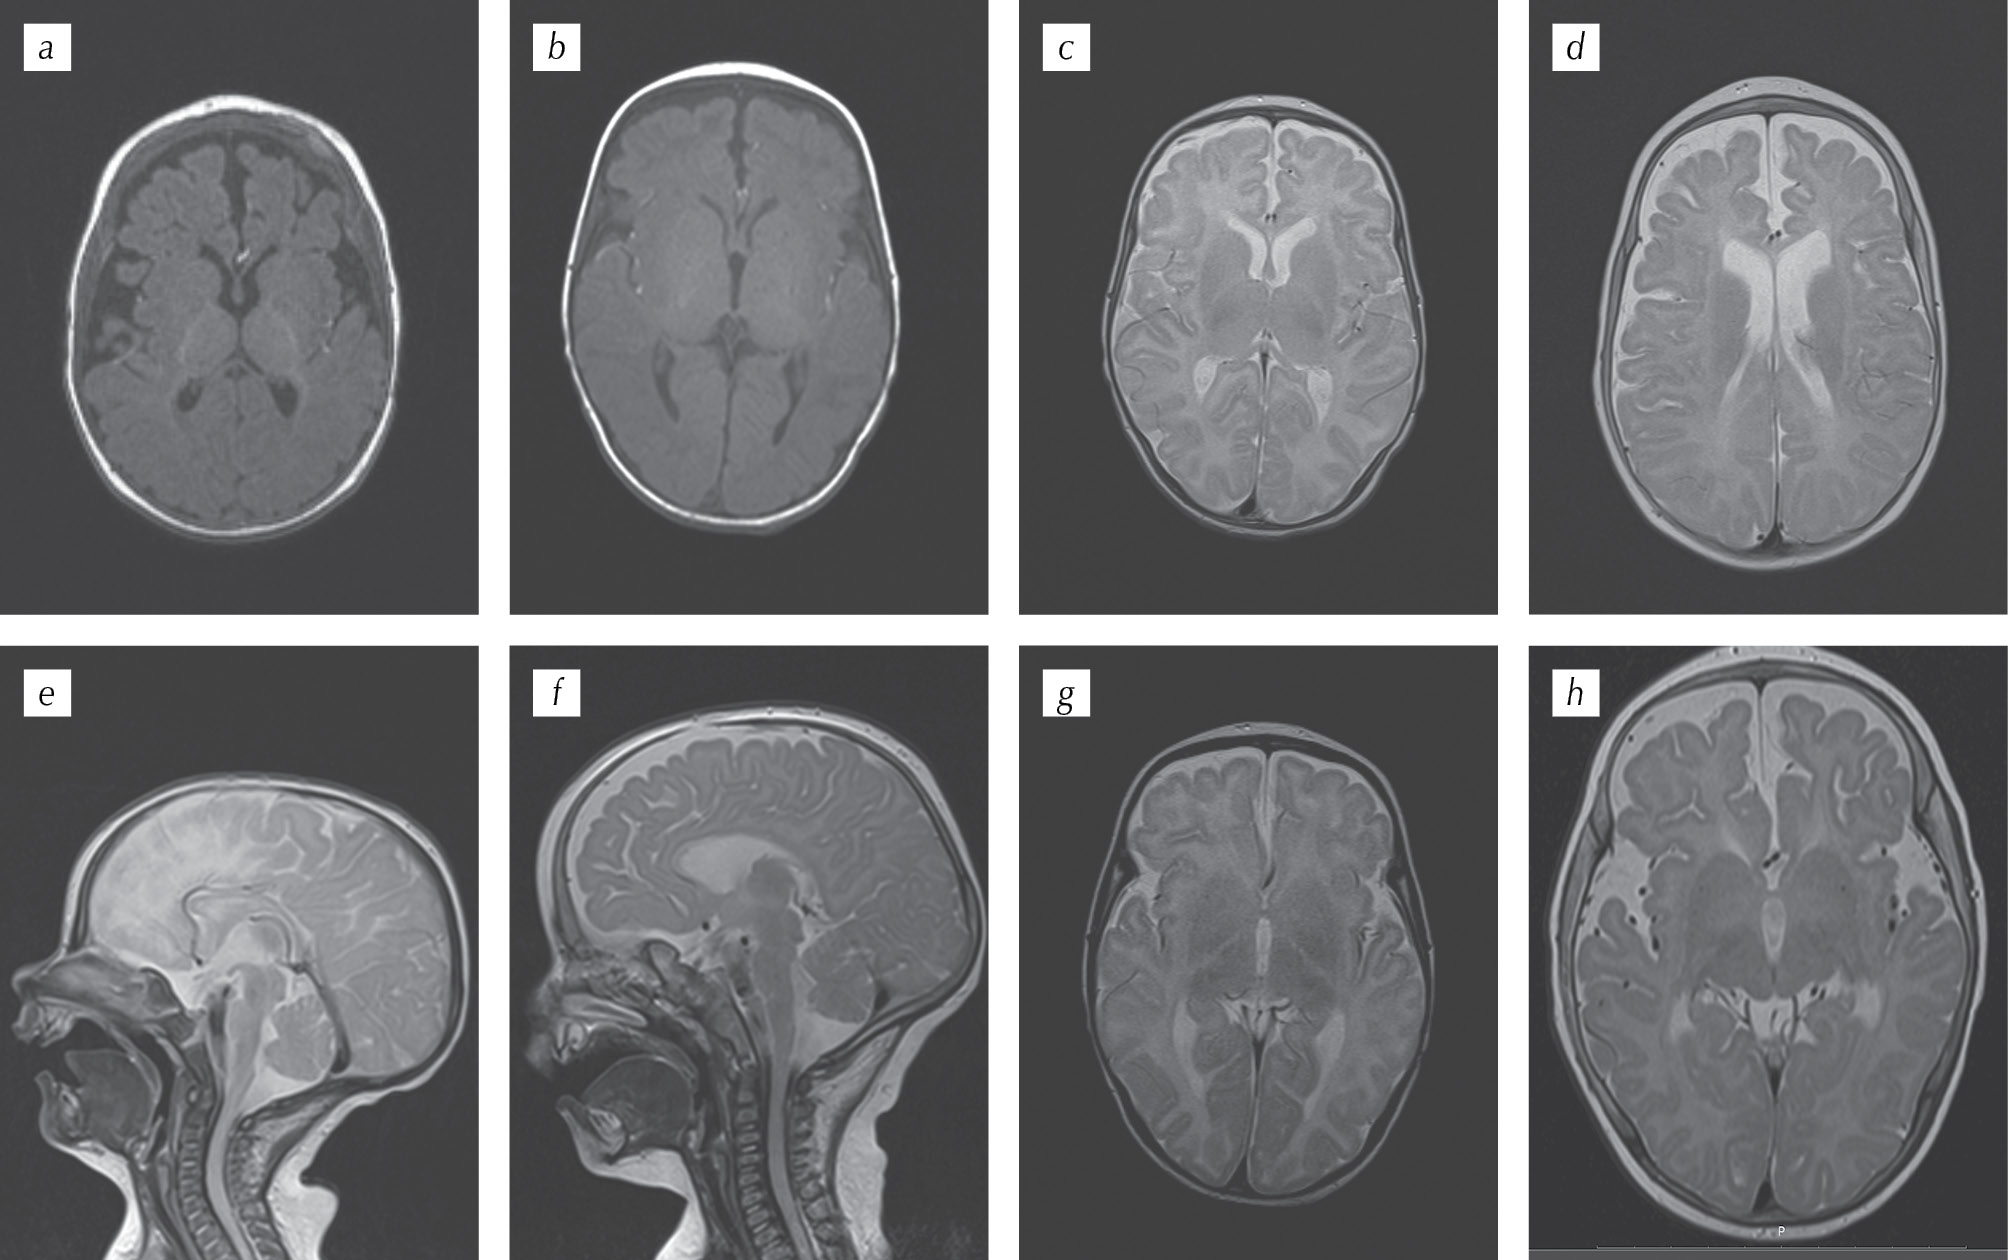

- МРТ головного мозга (8 мес.): атрофические изменения в лобно-височных отделах полушарий мозга (рис. 7, b, d, f); замедление миелинизации области ствола, заднего бедра внутренней капсулы (рис. 7, h). Проводили сравнение с ранними снимками МРТ (в возрасте 1 мес.). Выявлены атрофия лобно-височных отделов (рис. 7, a, c, e) и замедление миелинизации области ствола, заднего бедра внутренней капсулы (рис. 7, g).

Рис. 7. МРТ мальчика М. с синдромом кабуки 1-го типа в возрасте 1 мес. (a, c, e, f) и 8 мес. (b, d, f, h). Атрофические изменения в лобно-височных отделах полушарий мозга и замедление миелинизации области ствола, заднего бедра внутренней капсулы

Fig. 7. MRI of the boy M. with 1 type Kabuki syndrome at the age of 1 month (a, c, e, f) and 8 months (b, d, f, h). Atrophic changes in the frontal-temporal hemispheres of the brain and slowing myelination of the trunk, posterior limb of the inner capsule